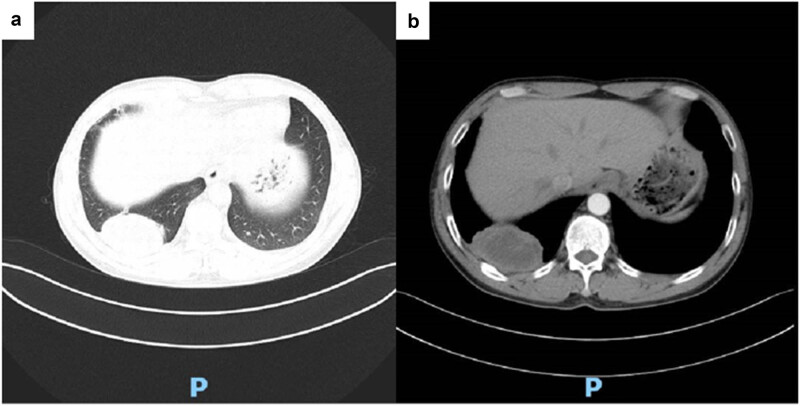

肺隐球菌病是一种由新型隐球菌或加蒂隐球菌引起的侵袭性真菌感染。它的临床表现和放射学表现通常是非特异性的,使得早期诊断具有挑战性。在这里,一个44岁的男性谁提出头晕和头痛的情况下,报告。最初的颅脑磁共振成像和胸部计算机断层扫描(平扫和增强扫描)提示肺癌伴脑转移。只有在肺肿块活检、细胞学涂片和组织病理学分析证实PC后,才确定了明确的诊断。术后给予抗真菌治疗,效果良好。本病例强调了在鉴别诊断中考虑PC的重要性,以便及时诊断和治疗,潜在地降低相关死亡率。

Pulmonary cryptococcosis (PC) is an invasive fungal infection caused by Cryptococcus neoformans or Cryptococcus gattii. Its clinical presentation and radiological findings are often non-specific, making early diagnosis challenging. Herein, the case of a 44-year-old male who presented with dizziness and headache is reported. Initial cranial magnetic resonance imaging and chest computed tomography (plain and contrast-enhanced) suggested lung cancer with brain metastasis. A definitive diagnosis was established only after a lung mass biopsy, followed by a cytological smear and histopathological analysis, confirmed PC. The patient was treated with antifungal therapy postoperatively and responded well. This case underscores the importance of considering PC in differential diagnoses to enable prompt diagnosis and treatment, potentially reducing associated mortality.